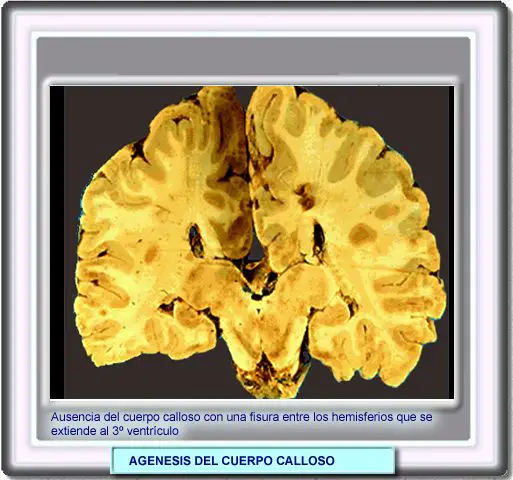

AGENESIA

DEL CUERPO CALLOSO